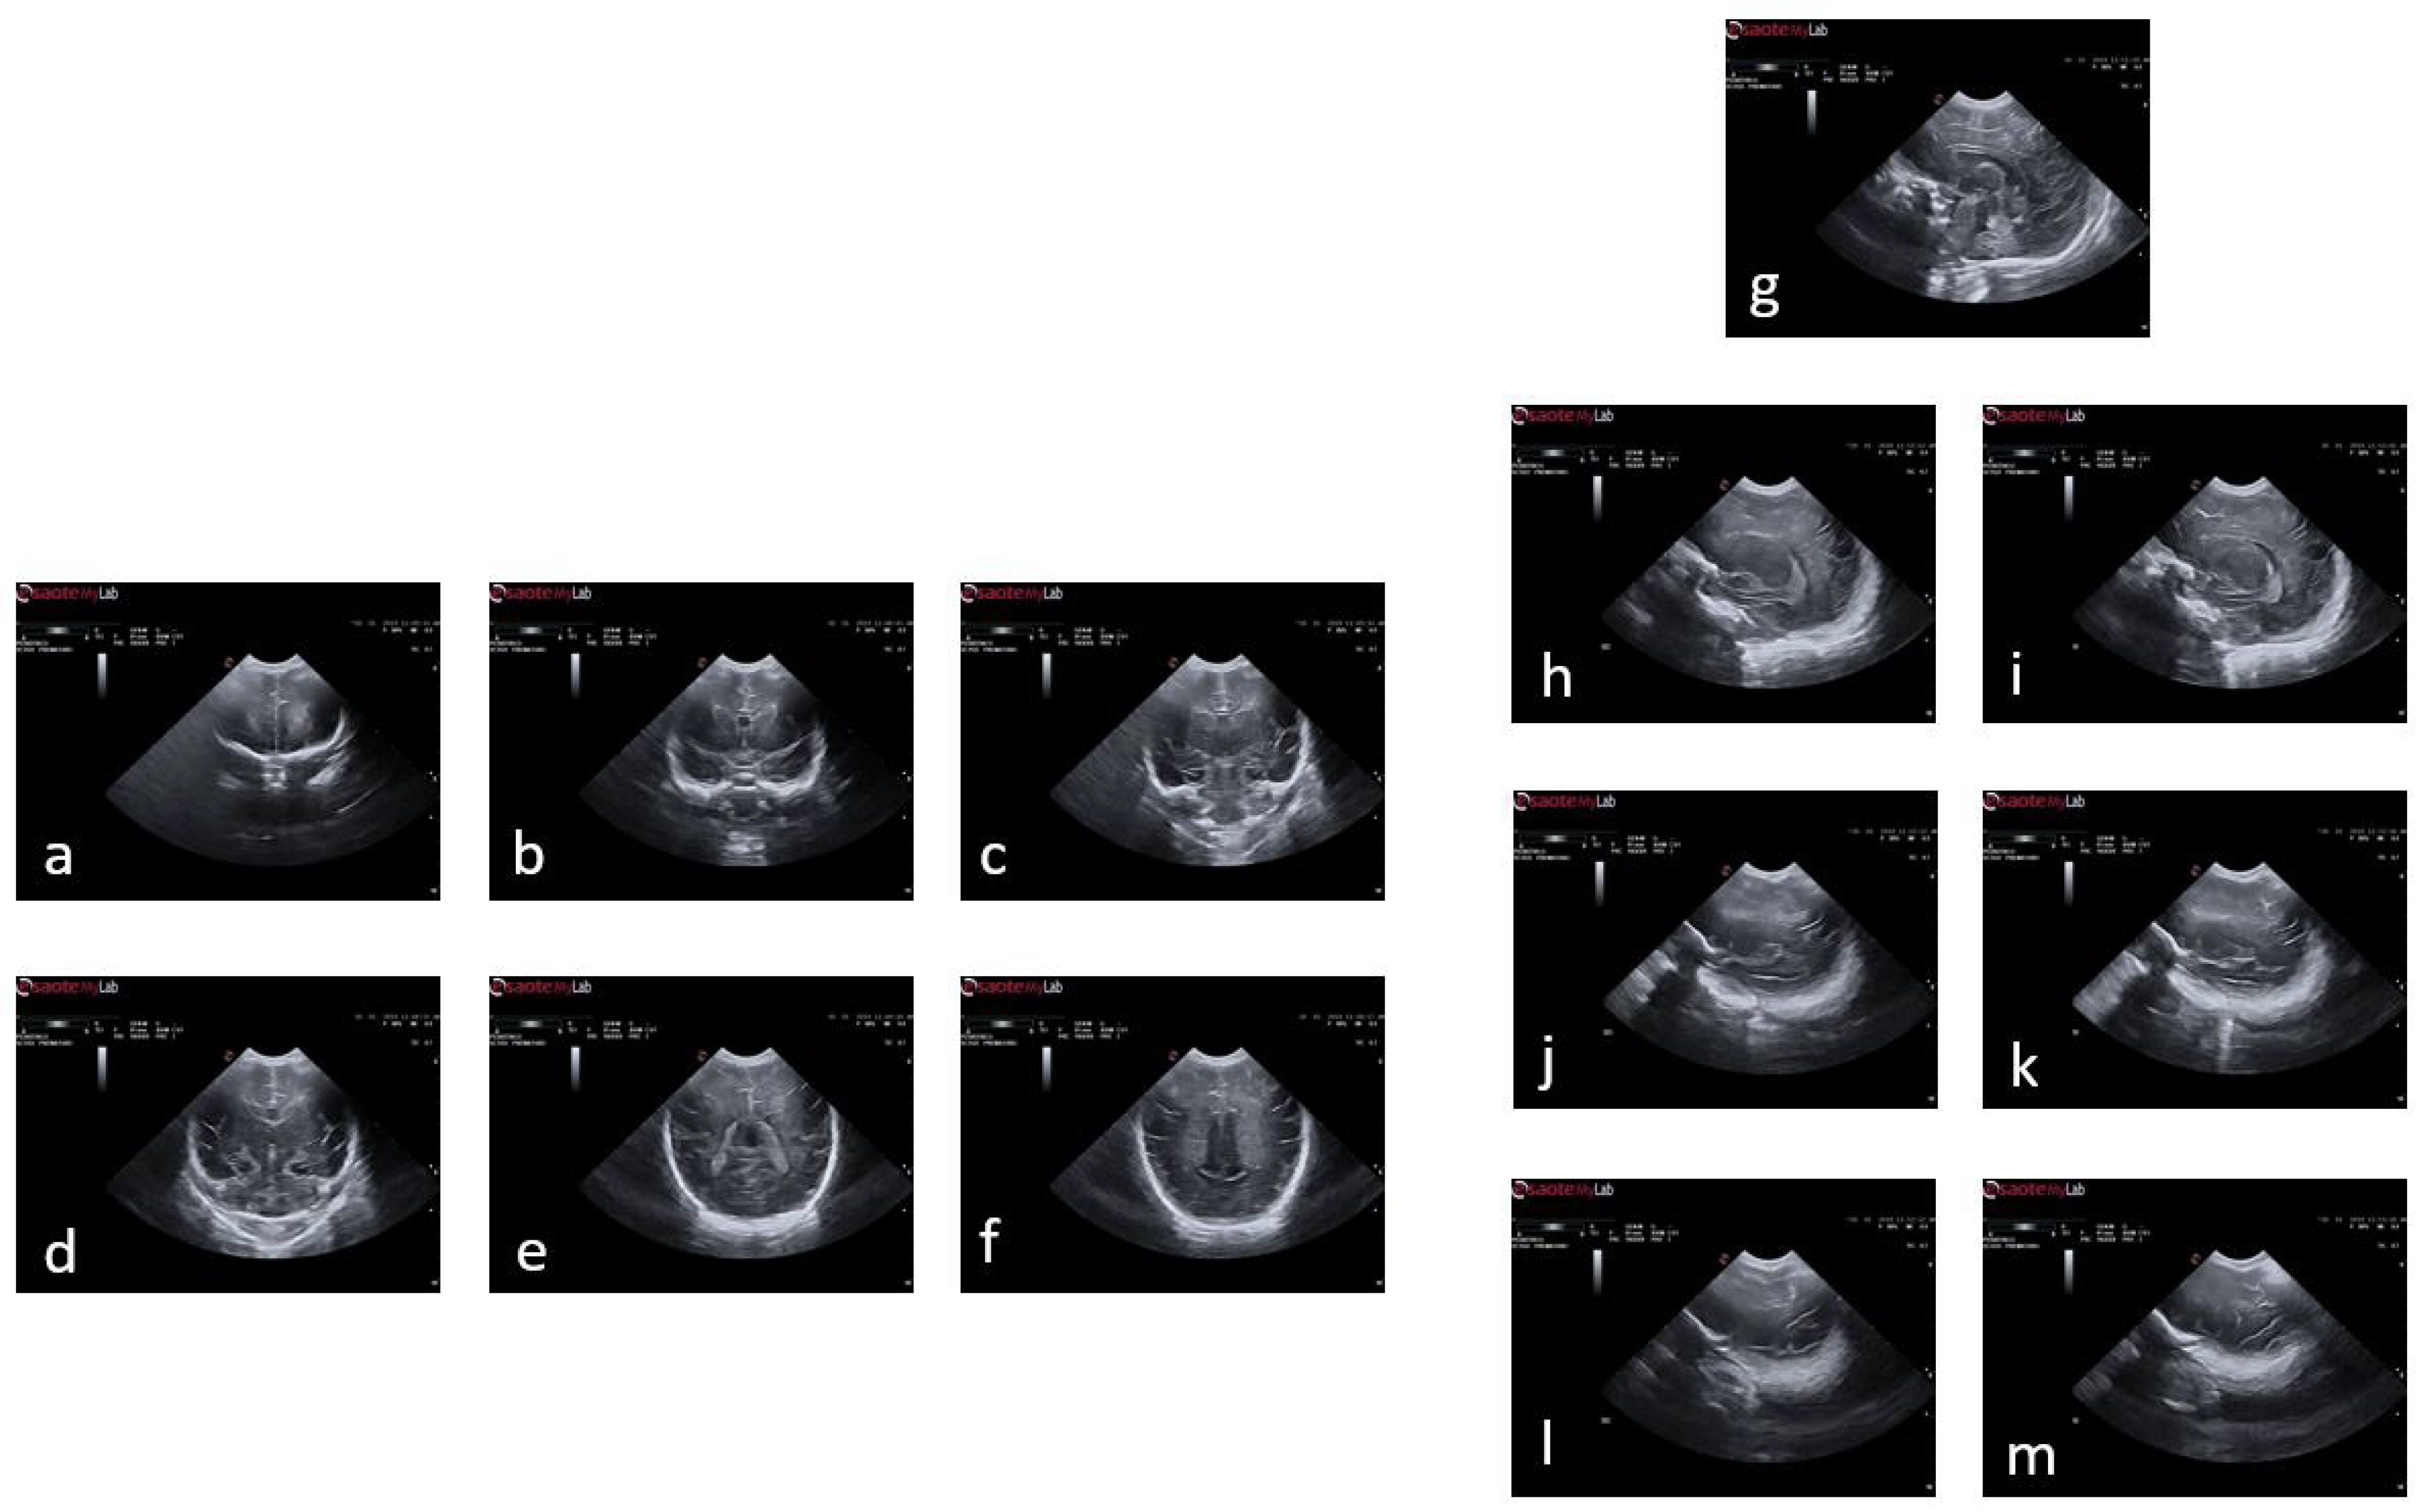

According to the World Health Organization (WHO), an estimated 13.4 million babies were born too early in 2020; that is more than one in ten babies [4]. Approximately 900,000 children died in 2019 of complications during preterm birth [5]. In this sense, it is worth mentioning that brain maturation is different when comparing a newborn that has completed nine months of gestation with a preterm baby that has grown outside the womb. Preterms are defined as babies born alive before 37 weeks of pregnancy are completed. There are sub-categories of preterm birth based on gestational age: Extremely preterm (less than 28 weeks), Very preterm (28 to 32 weeks), and Moderate to late preterm (32 to 36 weeks). An example of normal brain maturation in fetuses has been described using magnetic resonance imaging (MRI) techniques (Figure 1). To analyze the sulci of the brain during the maturation of the brain, the database is formed by two different planes, coronal or frontal and sagittal [6]. This concept refers to complex changes at specific stages of development whereby the cerebral cortex folds, forming sulci and gyri in order to increase the cerebral surface with a minor increase in volume. The process takes place during the last trimester of gestation, and it follows a specific sequence that allows us to date a specific brain base to its gyration status [7].

Figure 1. The spatio-temporal fetal brain magnetic resonance atlas (CRL fetal brain atlas) at six representative gestational ages: 22, 25, 28, 31, 34, and 37 weeks. Axial, coronal, and sagittal views of the atlas have been shown for each age point [7].